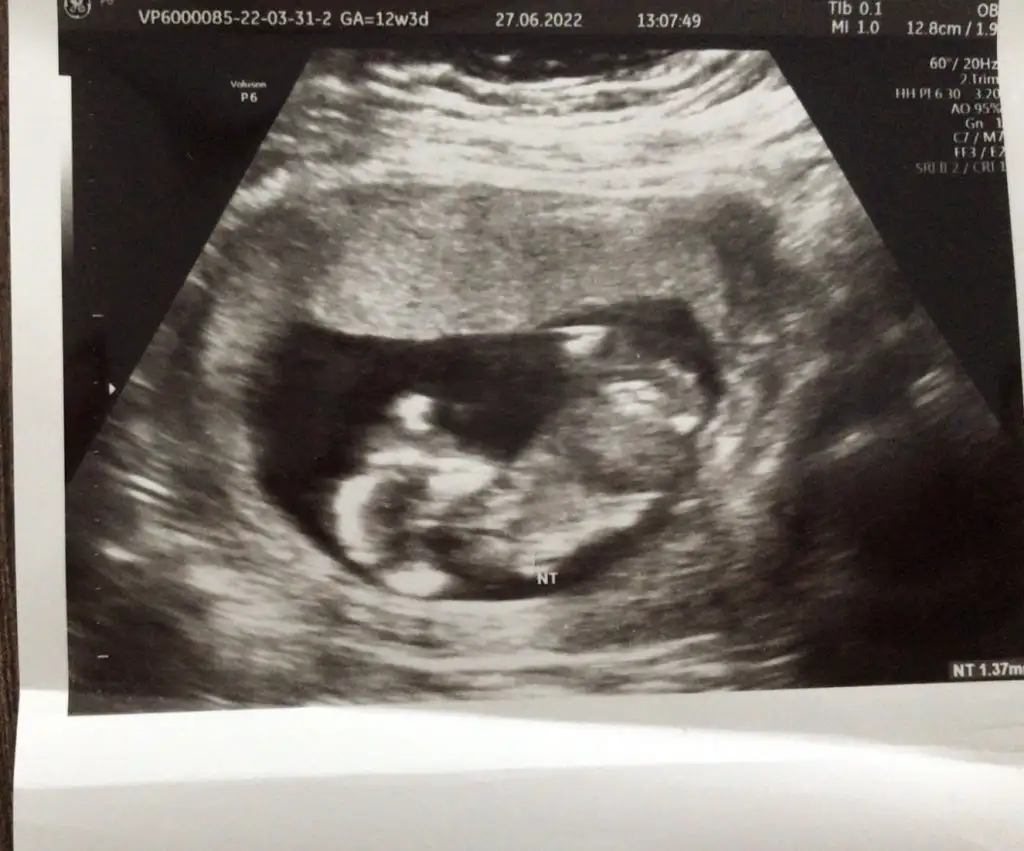

Arakadaşlar merhaba :)) 13+1 vajinal ultrason var elimde yardımcı olur musunuz lütfen tahminlerinizi merak ediyorum:)

• DA6BE62F-7903-4642-9A40-DBB7CB019A09.webp

DA6BE62F-7903-4642-9A40-DBB7CB019A09.webp

19,5 KB · Görüntüleme: 78

• 249DD539-0567-4C18-A5E6-361B869B3F4A.webp

249DD539-0567-4C18-A5E6-361B869B3F4A.webp

17,7 KB · Görüntüleme: 70

• 16F16BE8-8DBC-4E29-88E3-60E1EB14D657.webp

16F16BE8-8DBC-4E29-88E3-60E1EB14D657.webp

12 KB · Görüntüleme: 69